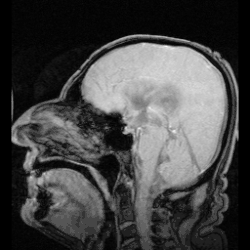

![]() The cerebrospinal fluid circulates in the subarachnoid space around the brain and spinal cord, and in the ventricles of the brain. | |

In humans, there is about 125–150 mL of CSF at any one time.[3] This CSF circulates within the ventricular system of the brain. The ventricles are a series of cavities filled with CSF. The majority of CSF is produced from within the two lateral ventricles. From here, CSF passes through the interventricular foramina to the third ventricle, then the cerebral aqueduct to the fourth ventricle. From the fourth ventricle, the fluid passes into the subarachnoid space through four openings – the central canal of the spinal cord, the median aperture, and the two lateral apertures.[3] CSF is present within the subarachnoid space, which covers the brain and spinal cord, and stretches below the end of the spinal cord to the sacrum.[3][4] There is a connection from the subarachnoid space to the bony labyrinth of the inner ear making the cerebrospinal fluid continuous with the perilymph in 93% of people.[5]

CSF occupies the subarachnoid space (between the arachnoid mater and the pia mater) and the ventricular system around and inside the brain and spinal cord. It fills the ventricles of the brain, cisterns, and sulci, as well as the central canal of the spinal cord. There is also a connection from the subarachnoid space to the bony labyrinth of the inner ear via the perilymphatic duct where the perilymph is continuous with the cerebrospinal fluid. The ependymal cells of the choroid plexus have multiple motile cilia on their apical surfaces that beat to move the CSF through the ventricles.